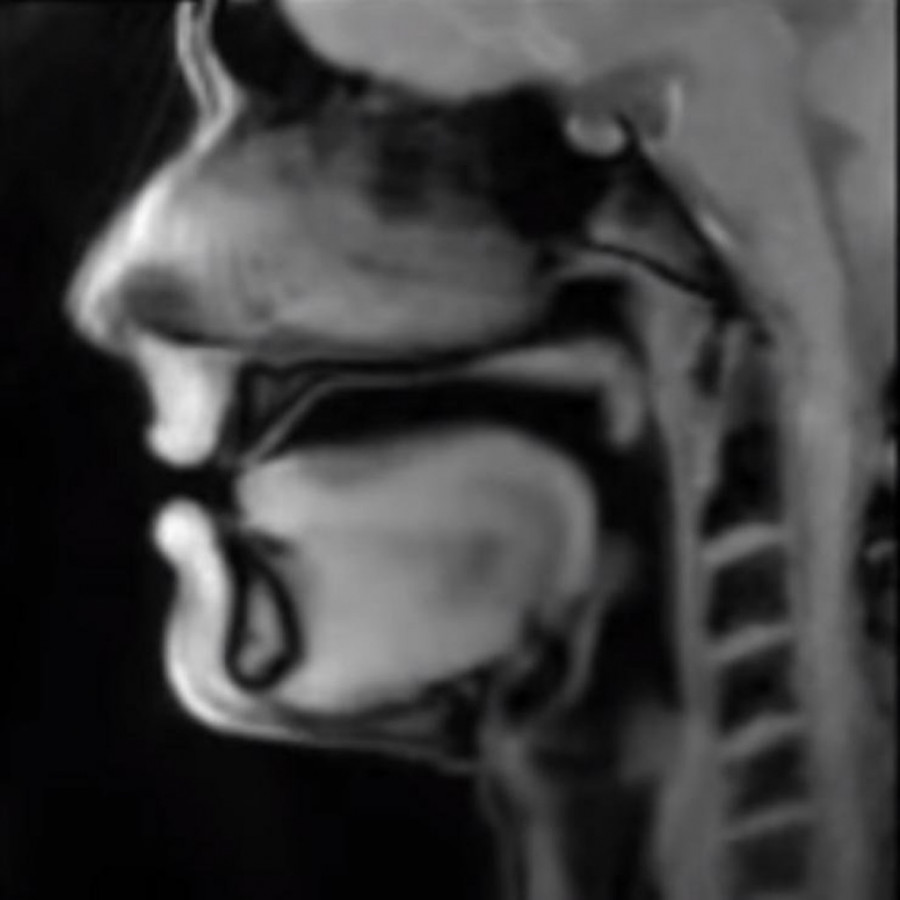

Foto: youtube.comSnimci su nastaie zahvaljujući novoj tehnologiji za magnetnu rezonancu koja stvara pokretne slike u realnom vremenu. Na Jutjub kanalu instituta objavljena su tri snimka - govora, pevanja i kucanja srca.

Jens Frahm, pionir magnetne rezonance i profesor na Maks Plank institutu za biofizičku hemiju u Nemačkoj, razvio je sistem FLASH2, koji koristi matematičke procese za rekonstrukciju skenova u pokretne slike.

-Tehnika je još jednom značajno ubrzala MRI skeniranje i omogućila do 100 sličica u sekundi, navode iz Instituta.

-Prvi put je moguće posmatrati zajedničke pokrete, govorne kretnje, procese gutanja ili otkucaje srca, kao i izvući zaključke o tome zašto koleno boli kada se savija, objasnili su sa univerziteta.

-Sad možemo da vizualizujemo procese koje dosada nismo videli, dodao je Frahm.